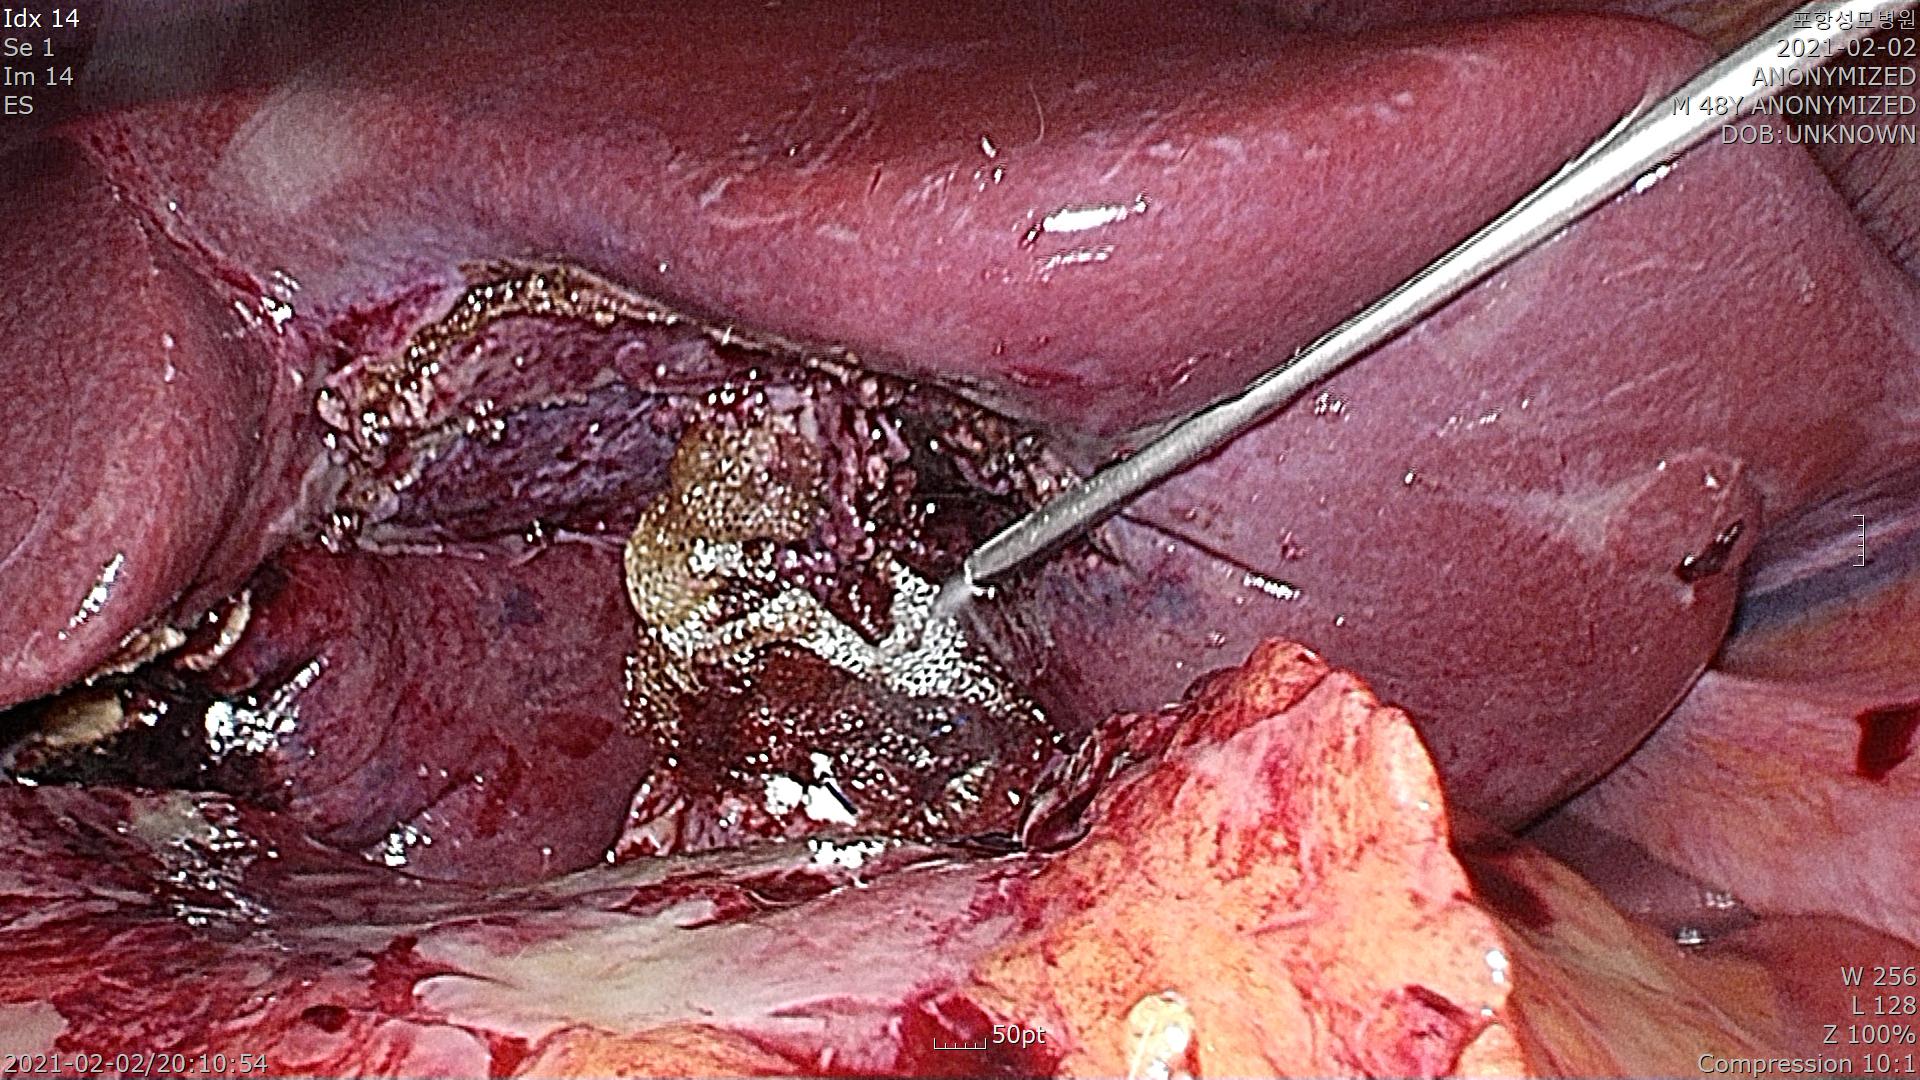

복강내에 지방조직이 담낭에 염증으로 유착되어 있습니다.

지방조직을 걷어내고 담낭을 확인합니다. 담낭이 거의 천공되기 직전입니다.

조심스럽게 지방조직과 담낭을 박리합니다.

간 후벽에 있는 담낭을 간으로부터 분리합니다. 염증이 심해 출혈도 꽤 있습니다.

담낭관을 확인합니다. 염증이 심한 수술때는 총담관 손상이 되지 않도록 조심해야 합니다.

담낭관이 두꺼워서 클립으로 결찰이 어려운 상황이라 Endoloop를 이용하여 담낭관을 결찰했습니다.

총담관 손상없이 잘 처리 되었습니다.

담낭을 떼어낸 간 후벽에 출혈이 심해 지혈을 하는데 시간이 꽤 걸렸습니다.